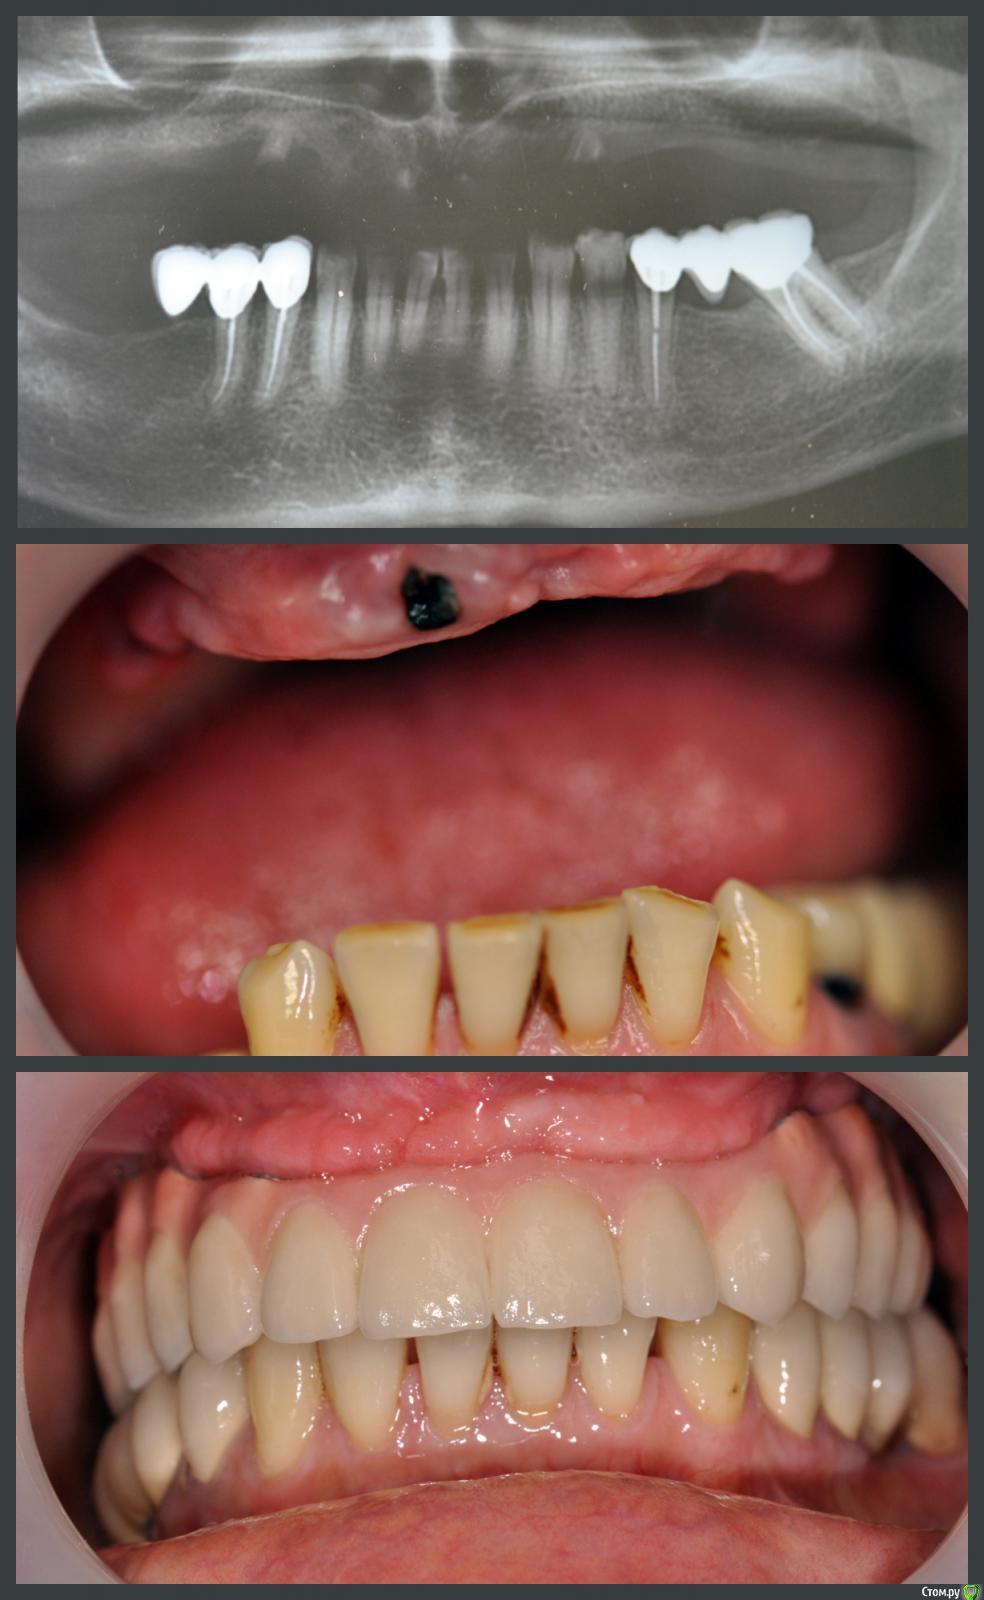

Сергей Таранов Опубликовано 28 ноября, 2016 Поделиться Опубликовано 28 ноября, 2016 Хронический периодонтит, фрактура корней 11,15,21,24. Удалены R 11,15,21,24. Проведена имплантация ВЧ в области 13-16, 23-26 с одномоментным открытым синус-лифтингом с использованием остеотропного материала mp3 (OsteoBiol by Tecnoss). Через 5 месяцев проведено протезирование на имплантах. 4 Ссылка на комментарий